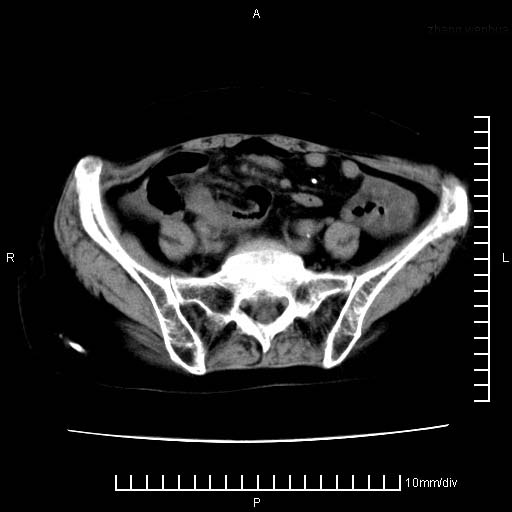

下腹疼痛2月,加重并呕吐2天,下腹压痛,反跳痛。白细胞1万2.

下腹至盆腔较大包块,与邻近肠管关系密切,下腹疼痛2月,加重并呕吐2天,下腹压痛,反跳痛。白细胞1万2.

由于没有做肠道准备很难分清是哪根肠管,但看位置考虑为升结肠回盲部的问题,我首先考虑化脓性阑尾炎,不除外结肠癌合并感染化脓。建议做增强进一步明确。

支持楼上意见:考虑回盲部慢性炎症,并包裹积脓肿。

盆腔脓肿伴盆腔积液

盆腔脓肿伴积液可能性大。

不知道大家可要注意下腹腔小肠旁不规则结节状灶,部分钙化,是否要考虑小肠腺癌.盆腔包块可能考虑脓肿.